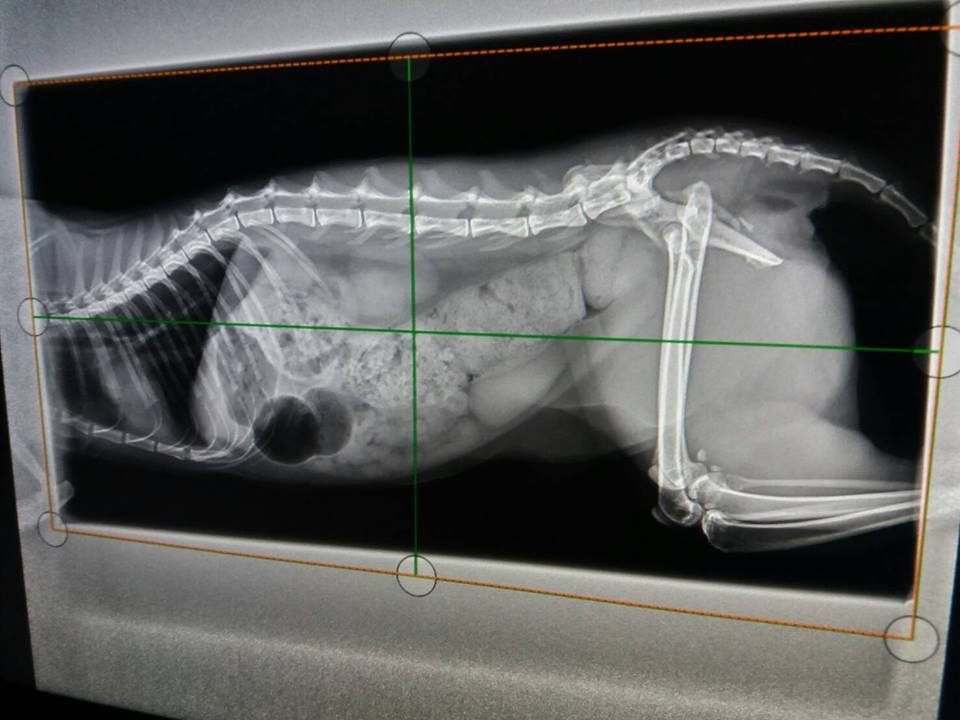

X光下發現大腸寬度變大,

認為有一可能導致艾咪雖有大便但無便意,等到積很久後,

後面大便已乾,